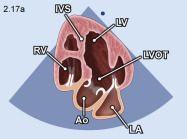

| 2.17. Mặt cắt 5 buồng từ mỏm |

||||||||

|

|

Cửa sổ siêu âm từ mỏm tim

Mặt cắt 5 buồng Ngả đầu dò hướng chùm siêu âm ra trước để bộc lộ đường ra thất trái |

Nhĩ trái (LA)

Van hai lá (MV) Thất trái (LV) Vách liên thất (IVS) Đường ra thất trái (LVOT) Thất phải (RV) Nhĩ phải (RA) |

|||||